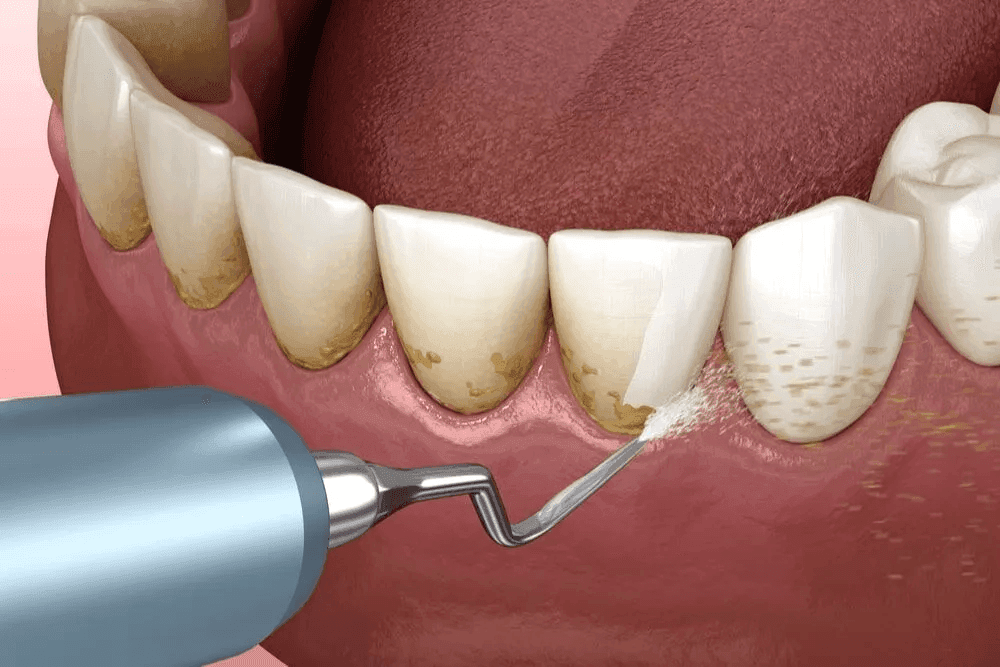

Dental scaling, often referred to as professional teeth cleaning, is a common dental procedure aimed at removing plaque and tartar (calculus) that build up on the teeth and along the gumline.During the procedure, the dentist or dental hygienist uses specialized instruments to carefully scrape away these hardened deposits, which cannot be removed with regular brushing or flossing. This process is essential for maintaining good oral health because it helps prevent gum disease, tooth decay, and other dental problems caused by bacteria accumulating in hard‑to‑reach areas.Having your teeth professionally cleaned on a regular basis—typically every six months as part of a routine dental check‑up—can play a major role in keeping your smile healthy and bright.

Dental scaling is a dental procedure carried out by a dentist or dental hygienist to remove plaque and tartar that have accumulated on the teeth and gums. The process typically includes the following steps:In general, dental scaling is a key part of preventive dental care and is essential for maintaining good oral health.